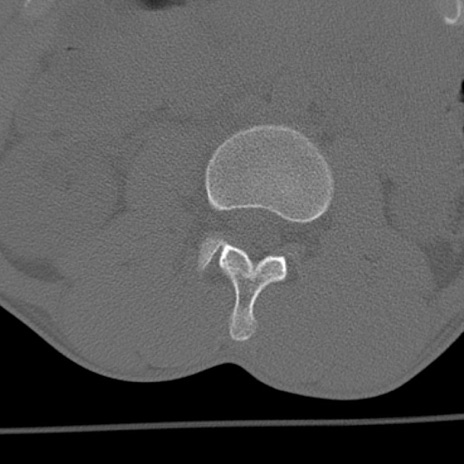

症例3 腰椎CT(横断像)

腰椎CT